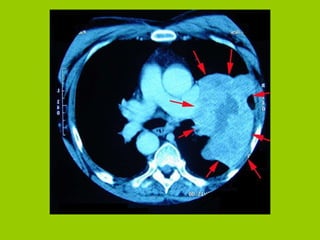

Bronchogenic Carcinoma

Normal Lung vs.Cancerous Lung